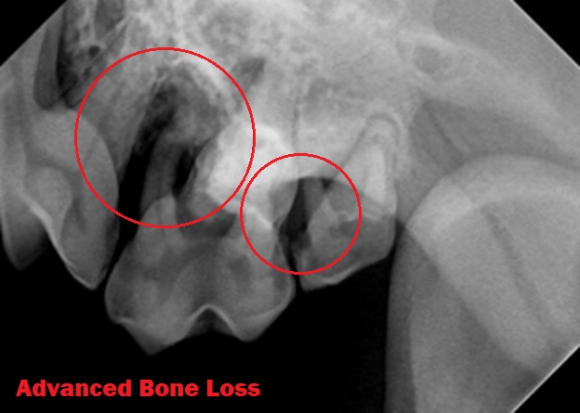

• Evaluation of periodontal disease:

• Height of the alveolar bone below the gum line in relation to the tooth

• Alveolar bone changes and degree of bone loss

• Size of the periodontal ligament space

• Presence or disappearance of the "lamina dura," the bone bundle attached to the periodontal ligament.